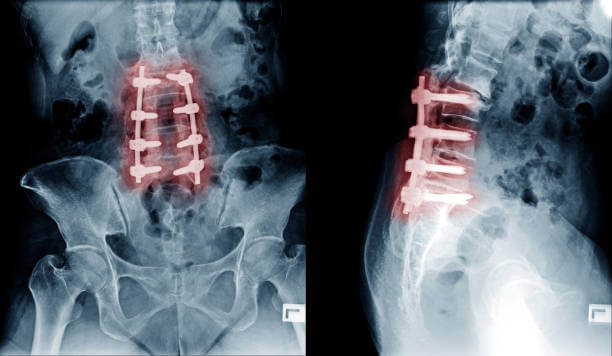

수술을 무조건 해야한다?

허리디스크에 대한 오해 중 가장 흔한 것이 '디스크가 약간 튀어나왔거나 심하지 않은 경우에는 수술 없이 치료가 가능하지만 많이 튀어나온 경우에는 반드시 수술적 치료를 해야 한다' 는 것입니다.

그러나 이것은 큰 오해입니다. 허리디스크가 많이 튀어나왔다고 반드시 수술로 치료해야 하는 것은 아니며, 비수술적 치료로도 충분히 회복이 가능합니다. 수술은 최후의 선택으로 고려되어야 하며 치료는 최대한 주의를 기울여 선택해야 합니다.

만약약 증상이 심한 경우에는 수술을 고려할 수도 있지만 대부분의 경우 비수술적 치료만으로도 충분히 호전될 수 있습니다. 그렇다면 어떻게 작동하는지 궁금할 것입니다. 크게 두 부류로 나눌 수 있습니다.

첫 번째는 신경성형술과 같은 시술이고 두 번째는 운동요법이나 물리치료와 같은 보존적 요법입니다. 우선 신경성형술은 경막외 유착 절제술이라고도 하는데 꼬리뼈에 특수 카테터를 삽입하고 통증이 있는 부위에 약물을 주입해 염증과 부종을 제거하고 유착 신경을 풀어주는 원리입니다.